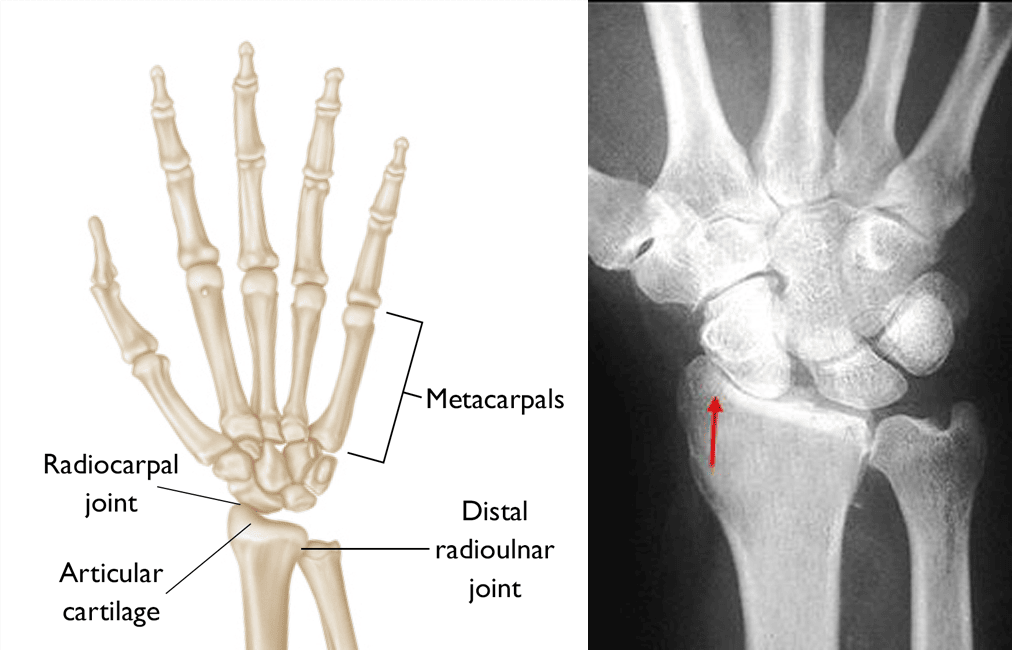

From anatomychart101.storage.googleapis.com

bones of wrist joint Wrist Joint Surgery get an overview of wrist replacement (wrist arthroplasty), including how wrist replacement surgery is. sometimes called arthroplasty, total wrist replacement involves removing damaged bones and cartilage in the wrist and. if your wrist is badly affected, moving your hand up, down and sideways may be very painful and it’ll be very difficult to twist your forearm to. Wrist Joint Surgery.